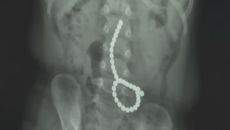

캑캑거리는 2살 아기 엑스레이 찍어보니...뱃속에 '자석 33개'

장난감 자석 33개를 삼킨 23개월 아이가 긴급 수술을 받고 무사히 퇴원했다. 18일 건양대병원에 따르면 지난 11일 23개월- 2025-06-19 10:28